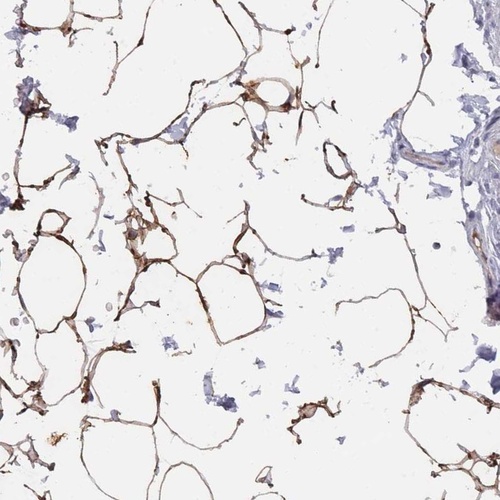

Immunohistochemical staining of human soft tissue shows strong positivity in adipocytes.